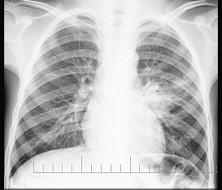

问题 3岁男孩,咳嗽、低热2周,不咯血、咳痰,X线检查如图,最可能的诊断是 ( )

选项 A.左肺炎症 B.左肺结核(Ⅰ型) C.左肺结核(Ⅱ型) D.左肺结核(Ⅲ型) E.左肺癌

答案 B